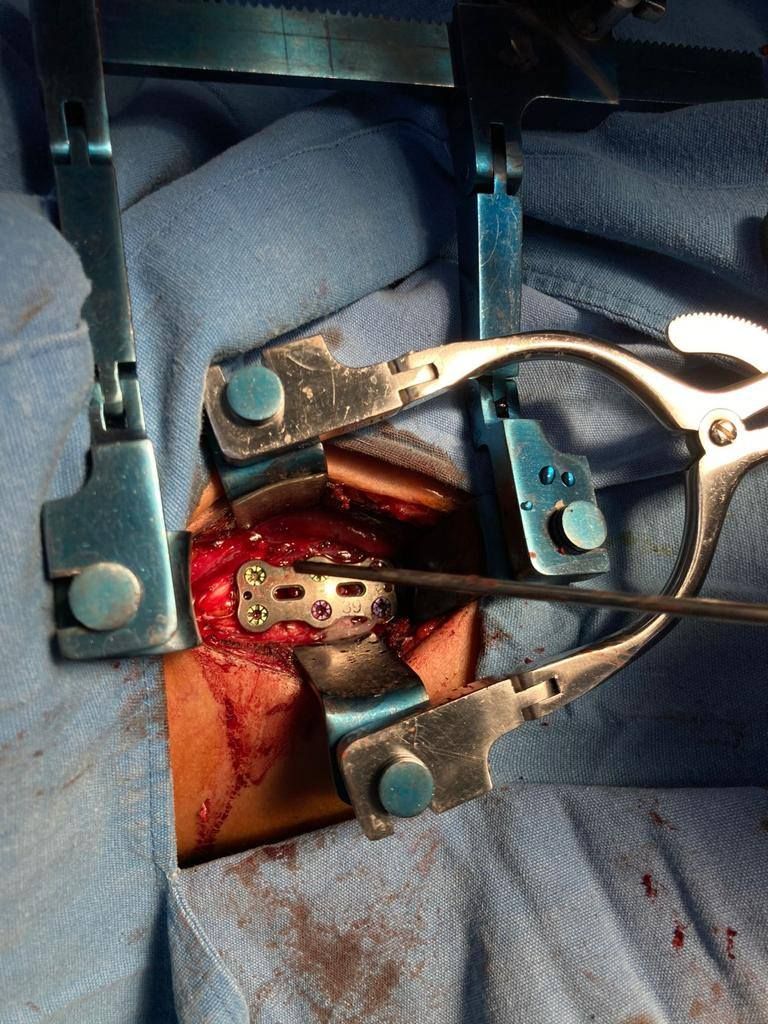

Neurocirugía general, cirugía de epilepsia, instrumentación de columna, cirugía funcional.

• Cirugía de columna

• Cirugía de columna mínimamente invasiva

• Cirugía de deformidades de la columna